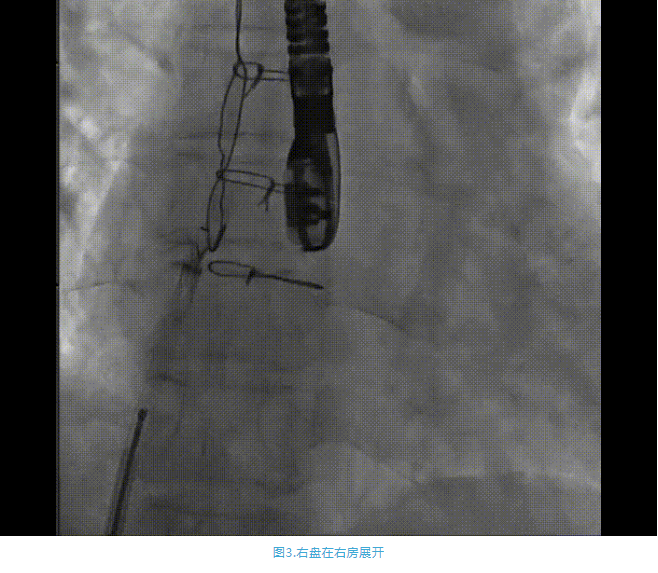

術(shù)中首先在局麻下穿刺股動脈、股靜脈,完成心導管檢查評估后轉(zhuǎn)為全麻,在食道超聲引導下穿刺房間隔,穿刺成功后將加硬導絲送入左上肺靜脈建立軌道,根據(jù)患者病情行球囊預擴張后植入6mm孔徑房間隔造孔支架,經(jīng)透視及食道超聲評估支架左右盤展開良好,夾持于房間隔兩側(cè),固定穩(wěn)定、位置良好,食道彩超顯示房水平右向左為主分流,分流孔直徑符合預期大小,心導管檢查評估達到預期效果,釋放造孔支架。術(shù)后12h患者下床活動,恢復順利,擬于近日完善術(shù)后評估后出院。